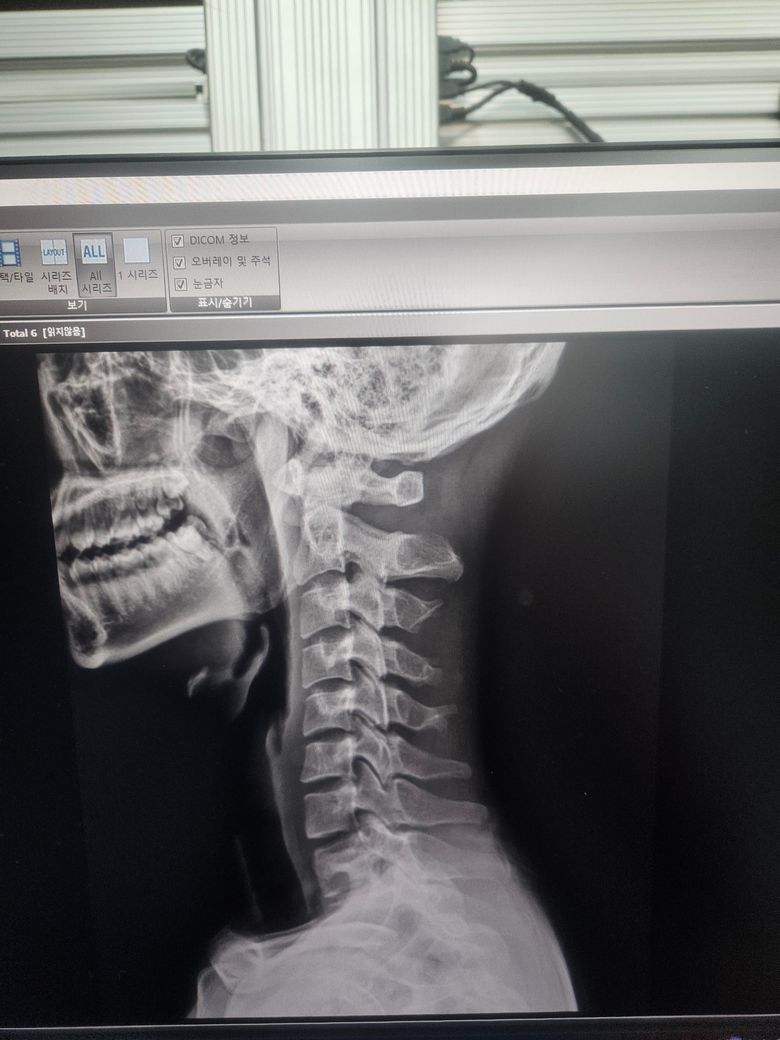

경추 불안정증인가요? 자세히 봐주세요 경추 1번 2번

경추 1번 2번 굴곡 신전시 이상이 있나요 제가 볼땐 많이 떨어지는것 같은데 다 아니라고 하시네요 전문의 답변 기다립니다 부탁드려요

올려주신 엑스레이 사진에서 특별한 이상 소견은 저명하지 않습니다.

이미 진료 시 이상이 없다고 설명을 들으셨다면 너무 걱정하지 마시기 바랍니다.